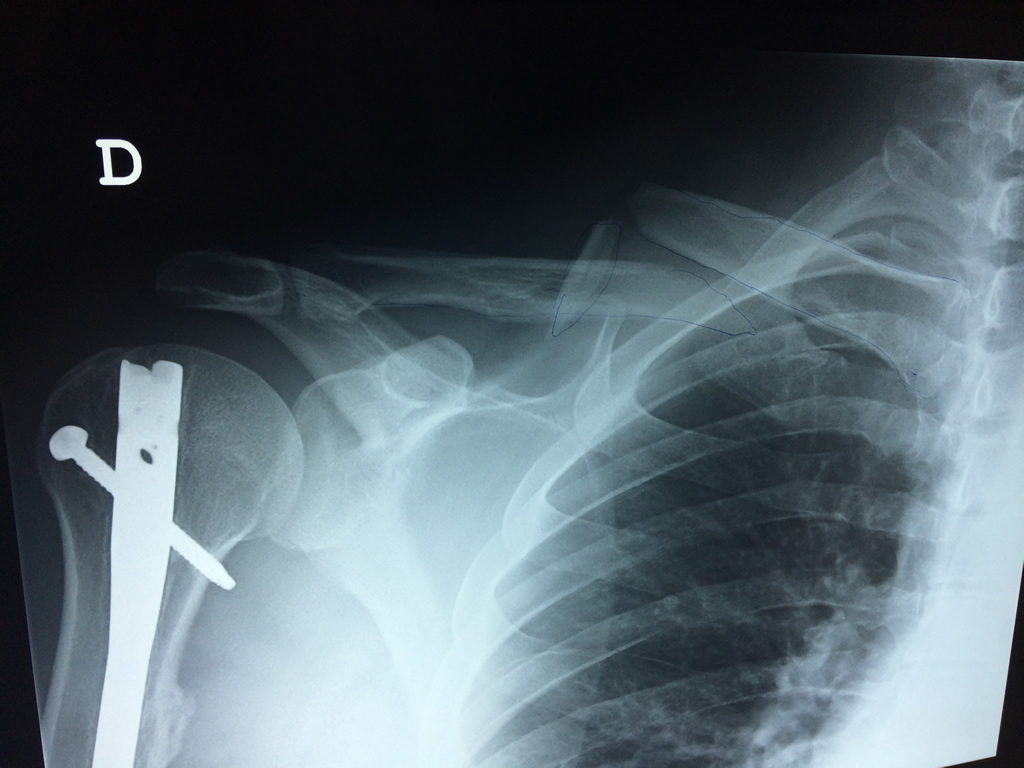

Cirugías de Calcaneo - Clavícula